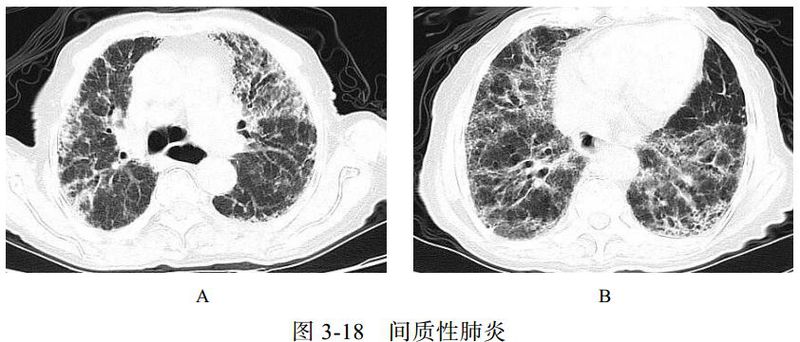

(四)间质性肺炎

肺间质纤维化性疾病包括一系列导致肺间质进行性纤维化的原发性或继发性结缔组织疾病,原发性主要为特发性肺间质纤维化,继发性主要包括系统性红斑狼疮、干燥综合征、类风湿关节炎等。特发性肺间质纤维化、系统性红斑狼疮、干燥综合征三种病变在影像学上表现相似,属于典型的“同影异病”,均表现为肺间质纤维化改变。细菌和病毒均可以引起间质性肺炎。

影像学表现:两肺支气管血管束增多,网格状及小点状影,周围夹杂多发蜂窝状囊状影、肺气肿及牵拉性支气管扩张,相应胸膜下小叶间隔增厚(图 3-18)。

图片